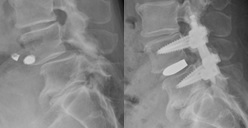

1)腰椎椎間板ヘルニア手術

内視鏡下椎間板摘出術(MED):内視鏡を用い、背中の小さな切開(約1.5㎝~2㎝)からヘルニアを摘出する手術です。従来の切開手術と比べ、筋肉の損傷が少なく、術後の痛みの軽減や早期の退院・社会復帰が期待されます。椎間板後方摘出術